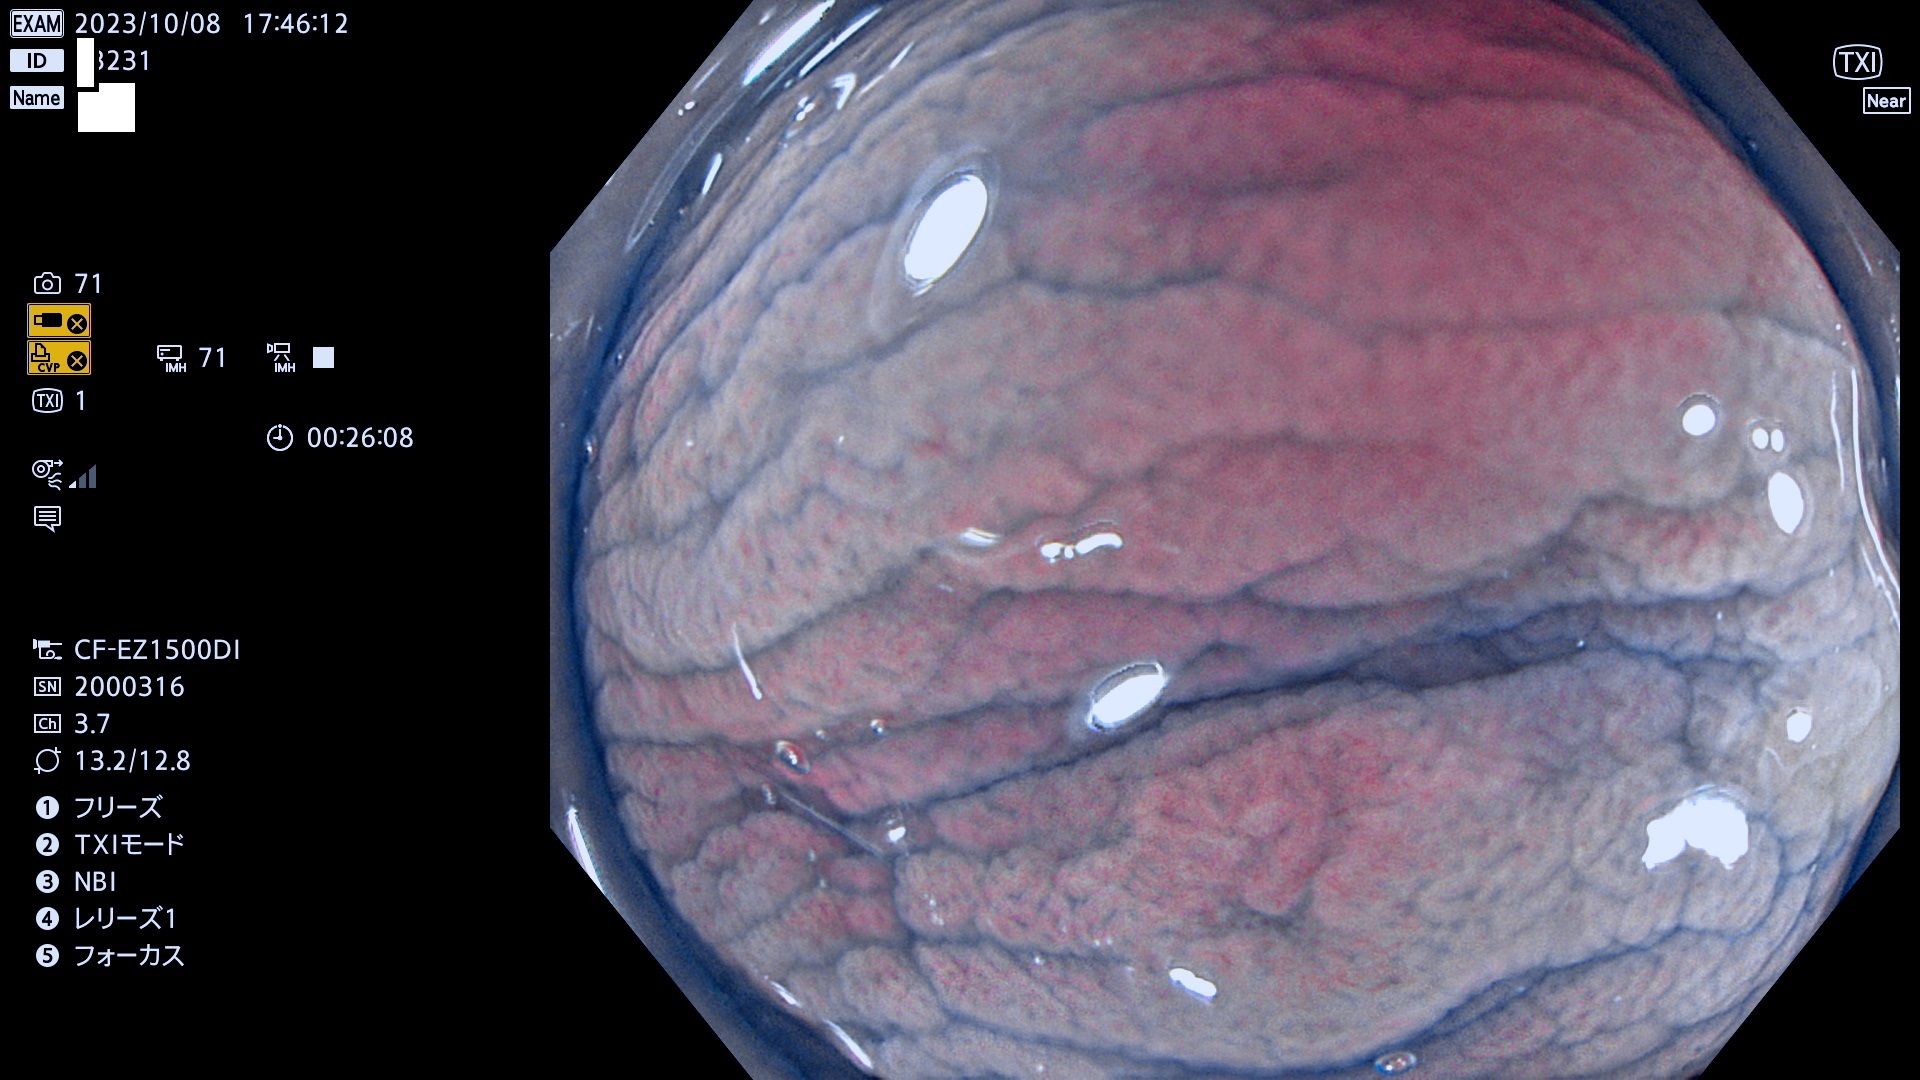

表面型腺腫(Flat Adenoma)の中で、完全に平坦な物をUb、陥凹している物をUcと呼びます。平坦隆起型(Ua)よりも、発見が難しく危険な病変です。このタイプは「内視鏡後・大腸癌の重要犯人」であり、この発見率は「腺腫発見率」よりも、重要な意味があります。

専門的)何故、陥凹していると危険? 癌遺伝子の変異が蓄積すると細胞分裂が盛んになり隆起するのでは?と通常は思われるでしょう。しかし実際は逆です。これは2022年の記事にある「細胞はストレスに直面したら細胞分裂を止める(細胞老化に入り休眠する)という生命の基本的現象」によるものです(Oncogene Stress)。細胞老化を起こすのが癌抑制遺伝子で、この安全装置(ブレーキ)が壊れると癌になります(休眠からの覚醒)。ですから陥凹は「まだ癌では無いが癌化の直前」を意味します。特に「小サイズなのに陥凹している」病変は短期間に腫瘍進化(⇒2021年記事)が起きたことを意味します(=ゲノム不安定性

専門的)Uc=De Novo癌? 内視鏡の解像度が低かった時代、このような説もありました。しかし今日の高精度内視鏡では良性の微小なUc型腺腫が日常的に見つかります。私見ですが「Ucこそが多段階発癌(Adenoma-Carcinoma Sequence)のMain Route」と考えます。

毎週の検査(木・金・土・日)に発見されたUb、Uc型・腺腫を、その週の日曜の夜にUPし1週間、提示します。

抽出の対象期間 2023年10月4日(木)〜10月9(月)の5日間(60件の検査)8件